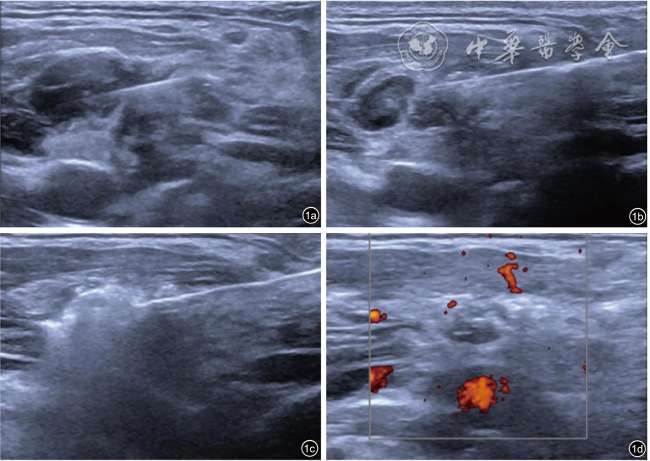

图2 甲状腺乳头状癌复发性颈部转移性淋巴结消融术前、术后超声图像。图a为术前颈部转移性淋巴结;图b为消融术后1个月复查图,可见混合不均匀回声区,以高回声为主,范围较原有淋巴结稍大;图c为术后3个月复查图,可见混合不均匀稍高回声区较前次复查缩小;图d为术后6个月复查图,与前次复查相仿;图e为术后12个月复查图,稍高回声区较前次复查缩小;图f为术后18个月复查图,原稍高回声区几乎显示不清,考虑消融灶几乎完全吸收 |